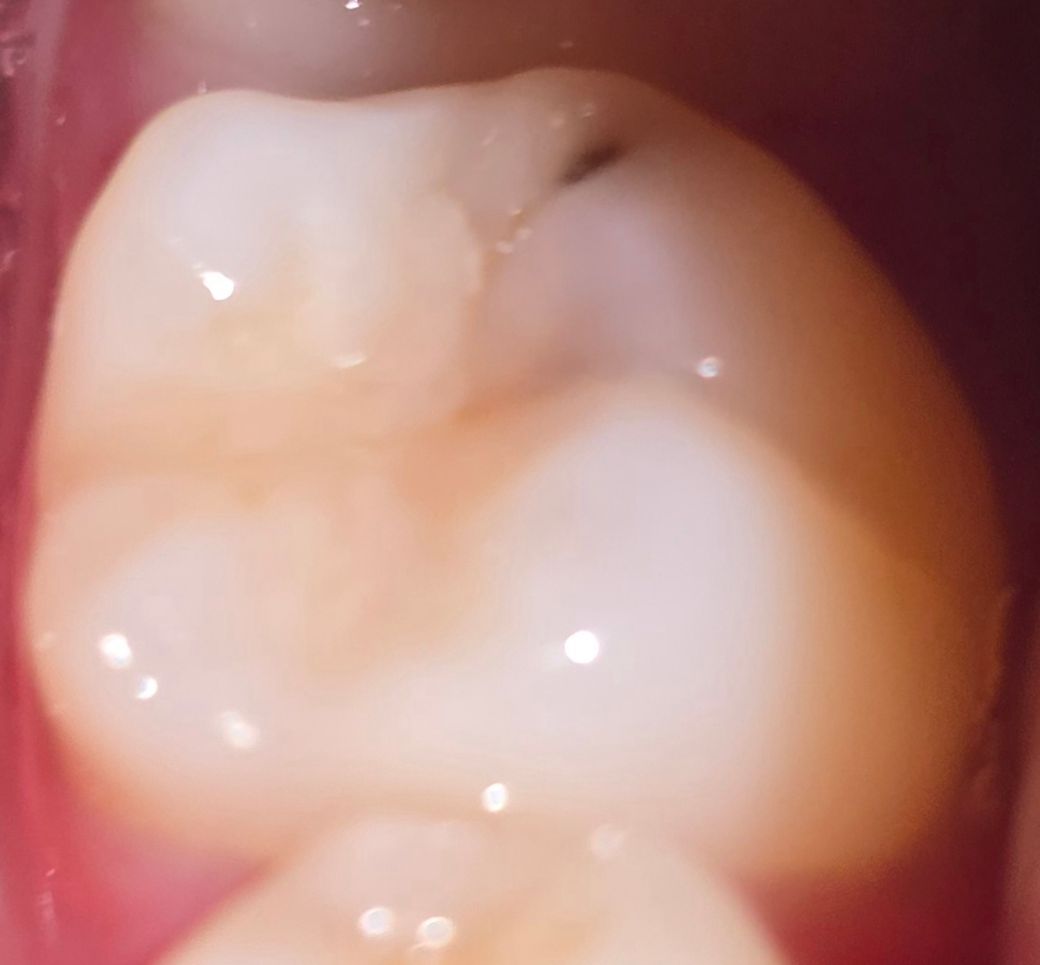

오른쪽 어금니에 검은 점 충치일까요?

이빨 닦은 후 갑자기 호기심이 생겨 핸드폰 불빛 켜고 거울에 비춰 이빨을 봤는데, 불과 며칠 전만 해도 보지 못했던 검은 점 같은게 오른쪽 어금니에 생겼더라고요. 처음엔 이물질인줄 알아서 이빨을 계속 닦았는데 안 없어지더라고요. 딱히 아프거나 답답하단 느낌은 전혀 없었는데, 충치일까요?

사진만으로 봤을 때에는 충치의 가능성이 높아 보입니다. 치과 가셔서 검사 받아보시는 게 좋겠습니다.

사진으로 보아 충치인 것 같습니다. 충치도 약간 깊게 진행된 것으로 보이니 가능한 빨리 치과에 가서 치료해야 합니다.

사진상으로 보면 충치인거 같습니다. 생각보다 깊을수 잇으니 치과에 가셔서 검진후 치료를 받아보시는게 좋을것같습니다.

사진으로 봤을 경우에는 충치로 보입니다. 하지만 범위가 큰 것 같아 보이진 않습니다. 간단하게 치료를 할 수 있으니 치과에서 진료를 받아보세요.